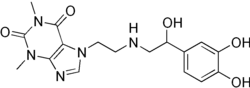

Theodrenaline

| Formula | C17H21N5O5 |

| Molar mass | 375.385 g·mol−1 |

Theodrenaline (INN), also known as noradrenalinoethyltheophylline or as noradrenaline theophylline, is a chemical linkage of norepinephrine (noradrenaline) and theophylline used as a cardiac stimulant.[1][2] It is sometimes combined with cafedrine.[1][2]